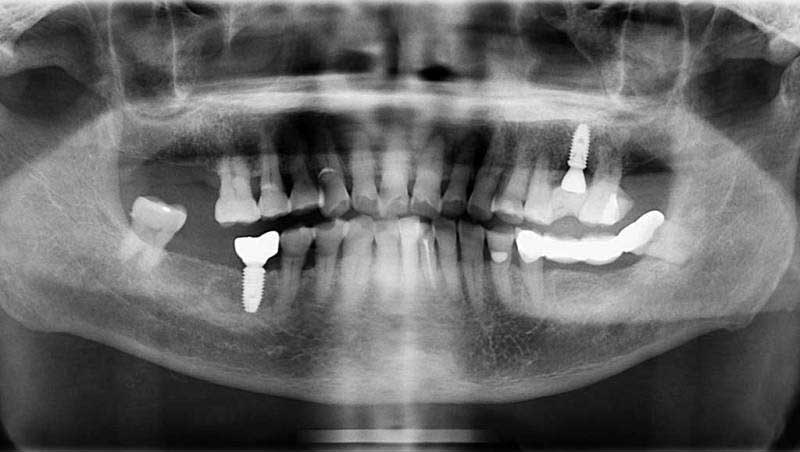

案例3